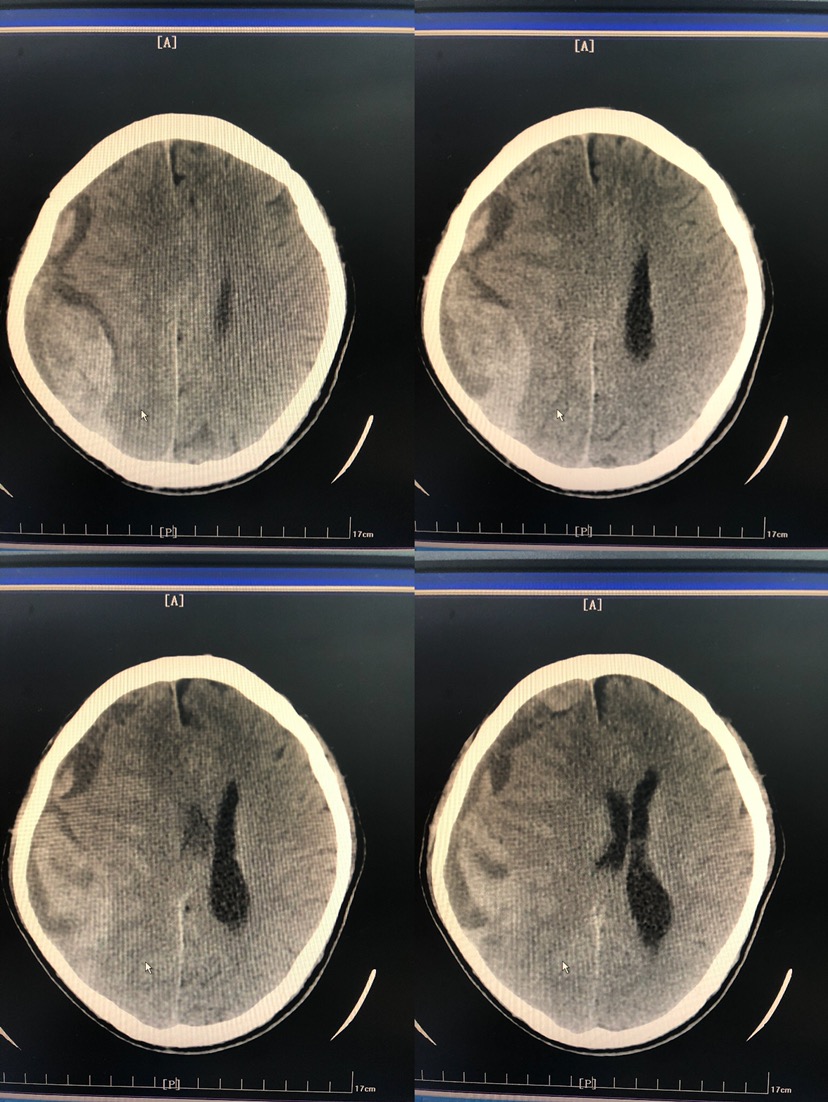

如图所见,CT及MRI提示均为硬膜外血肿。

考虑顶枕部血肿密度混杂,钻孔效果可能不佳。选择开颅手术治疗。

思考:1、该患者属慢行硬膜下血肿,长期刺激形成包膜,影像学表现呈梭形,易误认为硬膜外。